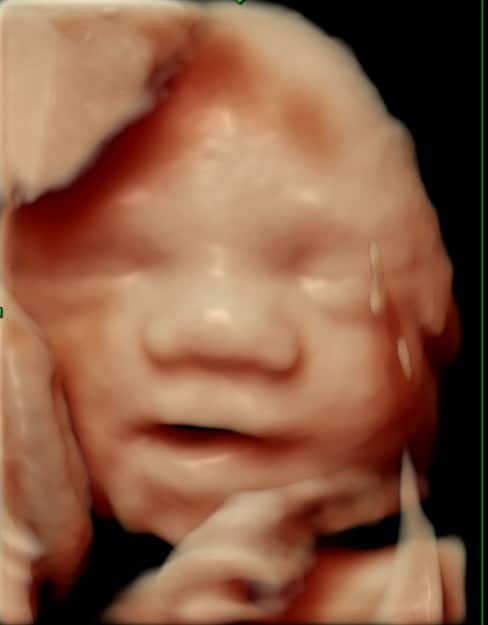

Tidlig scanning, kønsscanning, tryghedsscanning, 3D/4D og op/ned-scanning.

En graviditetsscanning er en ultralydsundersøgelse, hvor man ved hjælp af lydbølger kan se fosteret inde i livmoderen. Scanningen bruges til at bekræfte graviditeten, vurdere fosterets udvikling og tjekke, om alt ser normalt ud.

Hvad kan man se ved graviditetsscanninger?

Ved en graviditetsscanning kan man blandt andet se, hvor langt henne graviditeten er, om der er liv, antallet af fostre og hvordan fosterets organer og vækst udvikler sig. Senere i graviditeten kan man også se barnets køn, hvis man ønsker det.